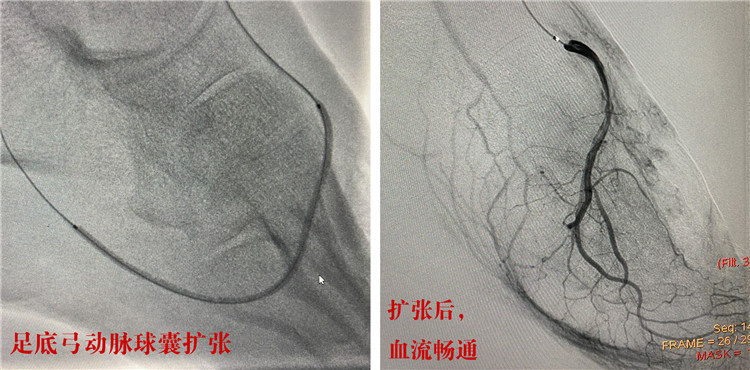

首先,由經(jīng)驗(yàn)豐富的放射科介入團(tuán)隊(duì)成功行下肢動(dòng)脈硬化血管球囊擴(kuò)張,血管開通后,陳先生的左下肢血流立刻恢復(fù)暢通;隨后,燒傷科為陳先生切除了左腳的干性壞疽,并給予潰瘍清創(chuàng)及腳面植皮;內(nèi)分泌科全程監(jiān)控,幫助患者控制血糖的同時(shí),耐心換藥護(hù)理。